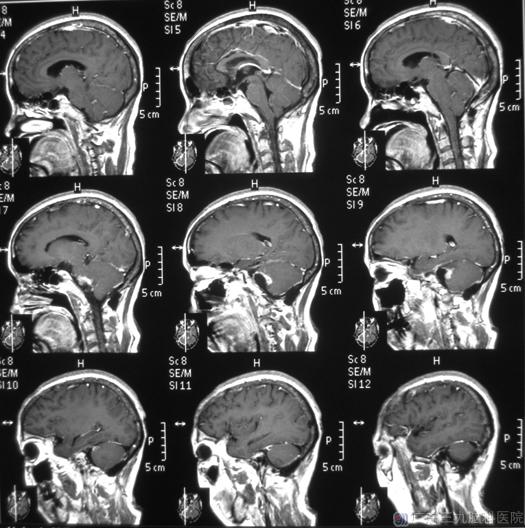

综合神经外科 鲁明主任主刀,在全麻下行右侧桥小脑角区肿瘤切除术,显微镜下见淡黄色肿瘤组织位于右侧桥小脑角,电生理监测下用超声刀分块切除肿瘤,对面神经、三叉神经、舌咽神经、副神经、迷走神经及脑干等重要结构均保留完整。术后病理结果:神经鞘膜瘤。

手术后